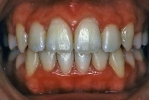

初診時